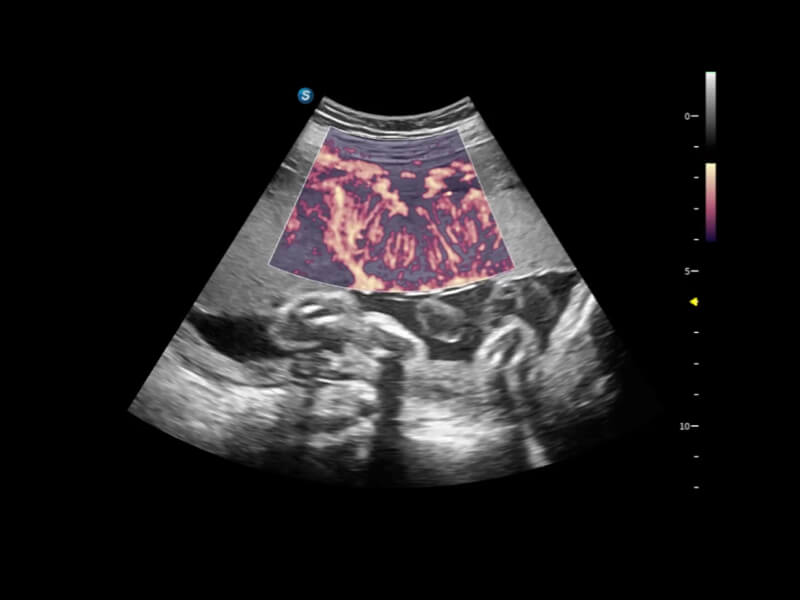

• FHR 高幀率血流成像

在傳統(tǒng)血流的基礎(chǔ)上優(yōu)化掃查和算法策略,能夠更好的抑制組織信息,提煉紅細(xì)胞運(yùn)動(dòng)信息,得到更高幀頻,高靈敏度和分辨率的血流信號(hào),還原更真實(shí)的血流動(dòng)力學(xué)。

• Bright Flow立體血流成像

通過光照模型,使二維血流顯示出立體的效果,增加血流的敏感性、成束性,減少外溢??梢院推渌煌难骷夹g(shù)聯(lián)合使用,融合不同技術(shù)的優(yōu)勢(shì)。輕松應(yīng)對(duì)微小血管,增強(qiáng)血流的立體效果,提升視覺敏感性。